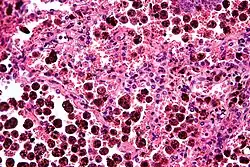

Comparison of pigmented pulmonary macrophages

| Disease | Macrophage name | Macrophage pigment appearance (HE stain) | Usual macrophage location | Associated medical history | Image | Image comment |

|---|---|---|---|---|---|---|

| Anthracosis | Black-brown granules | Interstitium (perivascular) | ![]() |

Black arrow shows interstitial anthracotic pigment. Nearby macrophages (white arrow) can be presumed to contain anthracotic pigment. | ||

| Respiratory bronchiolitis | "Smoker’s macrophages" | Yellow to light brown and finely granular[4] | Airways (especially respiratory bronchioles) | Tobacco smoking | ![]() |

Smoker's macrophage in center |